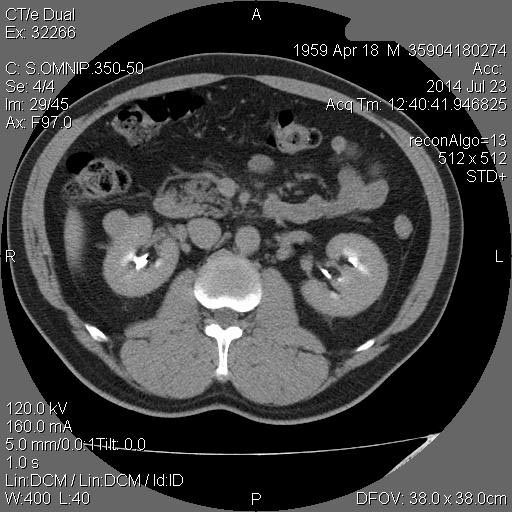

Образование в правой почке

Мужчина средних лет.Жалоб не предъявляет.

С его слов, 10 лет назад в правой почке находили кисту.

гипоэхогенное образование в среднем сегменте, деформирующее контур почки...наверное рак

Ответ каунасских радиологов - киста почки.

В том то и дело. Но тем не менее - это киста, анамнез уже несколько лет.besliu писал(а):Что-то на узи на кисту не похоже...

Кровотока ни грамма- Киста

Динамики нет, на последнем видео четко видна киста при включенной 2й гармонике